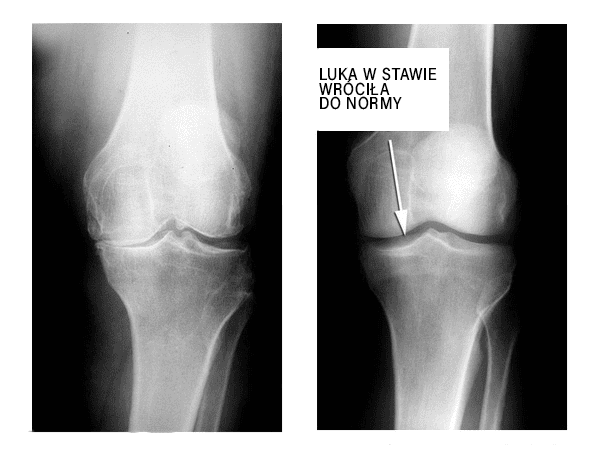

Na tym zdjęciu rentgenowskim chcę

pokazać efekt działania preparatu Artisan. Odbudowa uszkodzonego stawu po zastosowaniu kuracji kapsułkami Artisan: